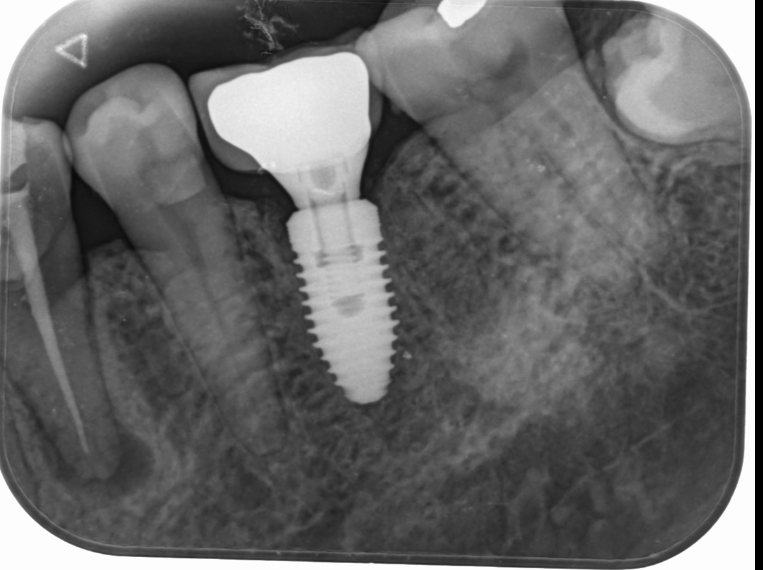

Dental implants are titanium posts that are surgically placed into the jawbone. They act as artificial tooth roots, providing stable support for crowns, bridges, or dentures. Implants integrate with the bone through a process called osseointegration, making them a durable and long-lasting solution for tooth replacement.

Implant Placement: During a surgical procedure, the dentist places the titanium implant into the jawbone. This procedure may require local anesthesia and is generally well-tolerated.

Healing Period: After the implant is placed, a healing period of several months is necessary for osseointegration to occur. During this time, the bone fuses with the implant, providing a strong foundation.

Abutment Placement: Once healing is complete, an abutment (a small connector) is attached to the implant. This piece will hold the replacement tooth.